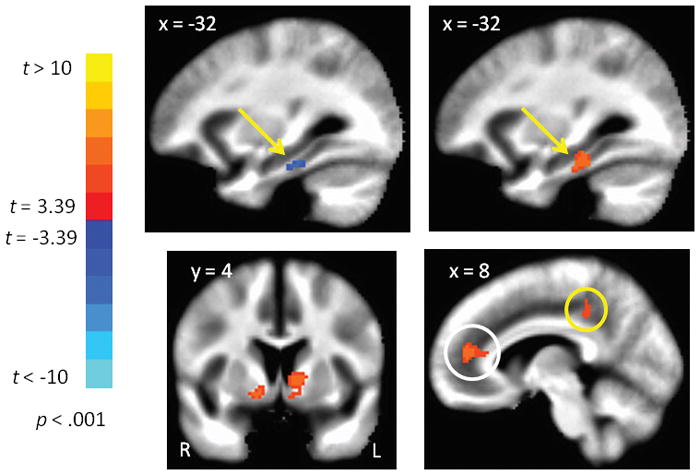

The top panel in Figure 1 shows the locations where FC of the ON was significantly stronger than the TN. These regions include the ventromedial PFC (vmPFC), subcallosal gyrus, retrosplenial cortex, and the hippocampus, each bilaterally. The bottom panel in Figure 1 shows where FC of the TN was significantly stronger than FC of the ON. These regions include the insula, thalamus, medial occipital cortex, middle temporal gyrus, cingulate gyrus, brain stem (red nucleus and pons), and cerebellar cortex. Table 1 tabulates the MNI coordinates and t-values for peak voxels from the contrast of the ON and TN. The unique brain regions belonging to the ON and TN, against a common baseline, have been reported in Tobia et al., 2016 [1]. Figure 2 shows regions where either the ON or TN was significantly correlated with age. For the ON, age was negatively correlated with FC to the parahippocampal gyrus (Figure 2 top left), but was positively correlated with FC to the caudate and nucleus accumbens (Figure 2, bottom left). For the TN, age was positively correlated with FC to the parahippocampal gyrus, which overlapped with the age-related decline in FC with the ON (Figure 2 top right), and age was also positively correlated with FC between the TN and both the anterior and posterior cingulate cortex (Figure 2 bottom right).

Figure 2.

Network functional connectivity correlated with age. Top panel: Functional connectivity of the olfactory network and the parahippocampal gyrus was negatively correlated with age (left), but this correlation was reversed for the trigeminal network in an overlapping swath of gray matter (right). Bottom panel: Functional connectivity of the olfactory network and the ventral striatum (basal ganglia) was positively correlated with age (left). Functional connectivity of the trigeminal network and the anterior and posterior cingulate cortex gyrus (white and yellow circles respectively) was positively correlated with age (right). Images show functional connectivity superimposed on the MNI template in radiological convention (left = right).